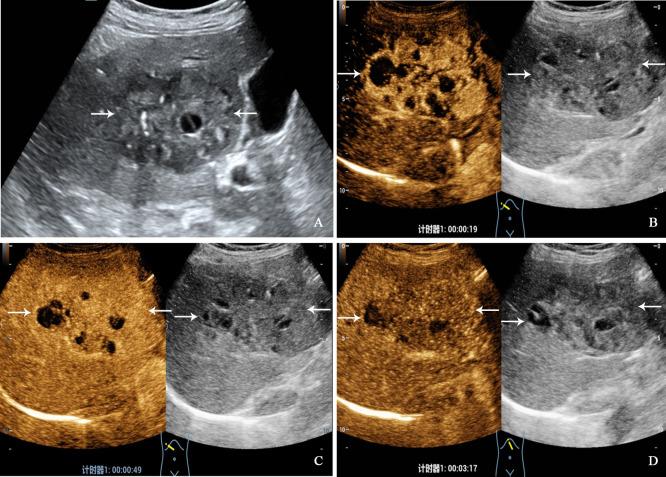

PHNET was more common in women (57.1%, 8/14 cases), and NBNC-HCC was more common in men (75.0%, 21/28) (=0.040). No significant differences were observed in etiology, tumor marker, and liver function between the two group (>0.05). Conventional ultrasound revealed that the tumor size of PHNET (10.1 ± 4.7 cm) was larger than that of NBNC-HCC (5.9 ± 3.8 cm) (=0.006). NBNC-HCC was predominantly hypoechoic, while the echogenicity of PHNET varied (=0.001). On CEUS, 57.1% (8/14) of PHNETs showed heterogeneous hyperenhancement, whereas 77.0% (21/28) of NBNC-HCC presented homogeneous hyperenhancement (=0.015). Furthermore, 35.7% (5/14) of PHNETs showed early washout (onset of washout <60 s), which was significantly different from that of NBNC-HCC (3.7%, 1/28) (=0.005).

CEUS is helpful in discriminating between PHNET and NBNC-HCC. PHNETs mainly present as a single mass with a large size (>10 cm) in the liver. The CEUS showed that most PHNETs exhibited heterogeneous enhancement in the arterial phase, washout in the portal venous and late phases and early washout being more likely than NBNC-HCC. However, more imaging features need to be evaluated in a larger sample.

PHNET在女性中更常见(57.1%,8/14例),而NBNC-HCC在男性中更常见(75.0%,21/28)(P=0.040)。两组在病因、肿瘤标志物及肝功能方面无显著差异(P>0.05)。常规超声显示,PHNET的肿瘤大小(10.1±4.7 cm)大于NBNC-HCC(5.9±3.8 cm)(P=0.006)。NBNC-HCC主要为低回声,而PHNET的回声各异(P=0.001)。在CEUS上,57.1%(8/14)的PHNET表现为不均匀高增强,而77.0%(21/28)的NBNC-HCC表现为均匀高增强(P=0.015)。此外,35.7%(5/14)的PHNET表现为早期廓清(廓清开始时间<60秒),这与NBNC-HCC(3.7%,1/28)有显著差异(P=0.005)。

CEUS有助于鉴别PHNET与NBNC-HCC。PHNET主要表现为肝脏内单个较大(>10 cm)肿块。CEUS显示,大多数PHNET在动脉期表现为不均匀增强,在门静脉期和延迟期廓清,且比NBNC-HCC更易出现早期廓清。然而,需要在更大样本中评估更多的影像学特征。